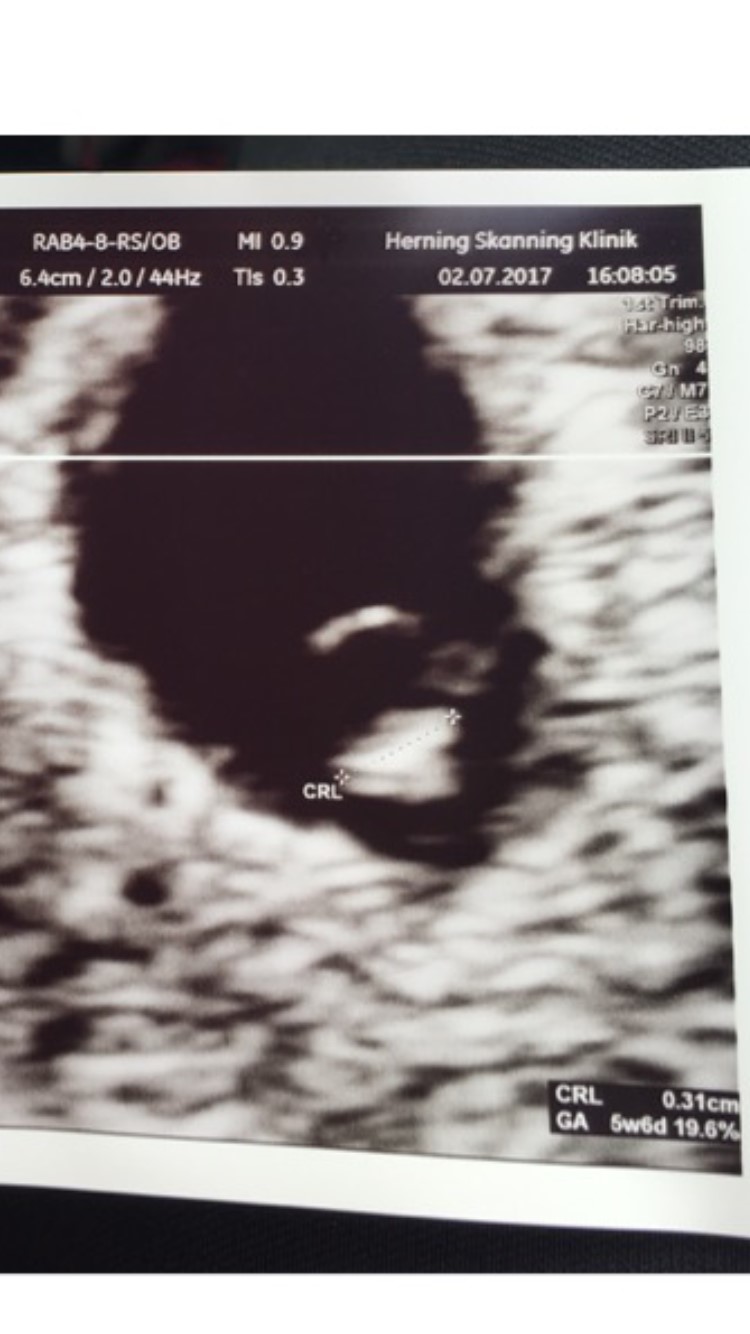

Jeg var til scanning idag. Skulle være 7+2

Men dette(se billeder) var det eneste de kunne se ved indvendig scanning. Hvad kan dette betyde og andre der har prøvet det?

Billed er lånt fra nettet da jeg ikke fik et med.

Her er et billede fra da jeg var 6+3

jeg blev selv sat tilbage ved tidlig scanning og der var ikke meget mere at se end det billede du viser. Troede jeg var 7+ men var åbenbart kun 5+4-6 i følge scanningen. En uge senere var det hjerteblink og nu i uge 30 er der liv og fest i maven..

Sådan her så det ud ved mig i uge 6+0 og 8+0 :-)

Disse to billeder er fra da jeg var 5+6 og var til tidlig scanning (skal igen på onsdag). Også selvbetalt.

Vi så fosteret med blommesæk og et lille meget kraftigt bankende hjerte, og hørte endda også hjertelyd.

Men du kan se at mit det ene billede ligner dit billede en del, og lægen som scannede mig (som desuden er overlæge på Herning Sygehus og yderst kompetent), sagde at der hvor det ligner en rund cirkel, der er det fosteret med blommesækken man kan se, det er taget fra en anden vinkel end det andet billede du kan se.